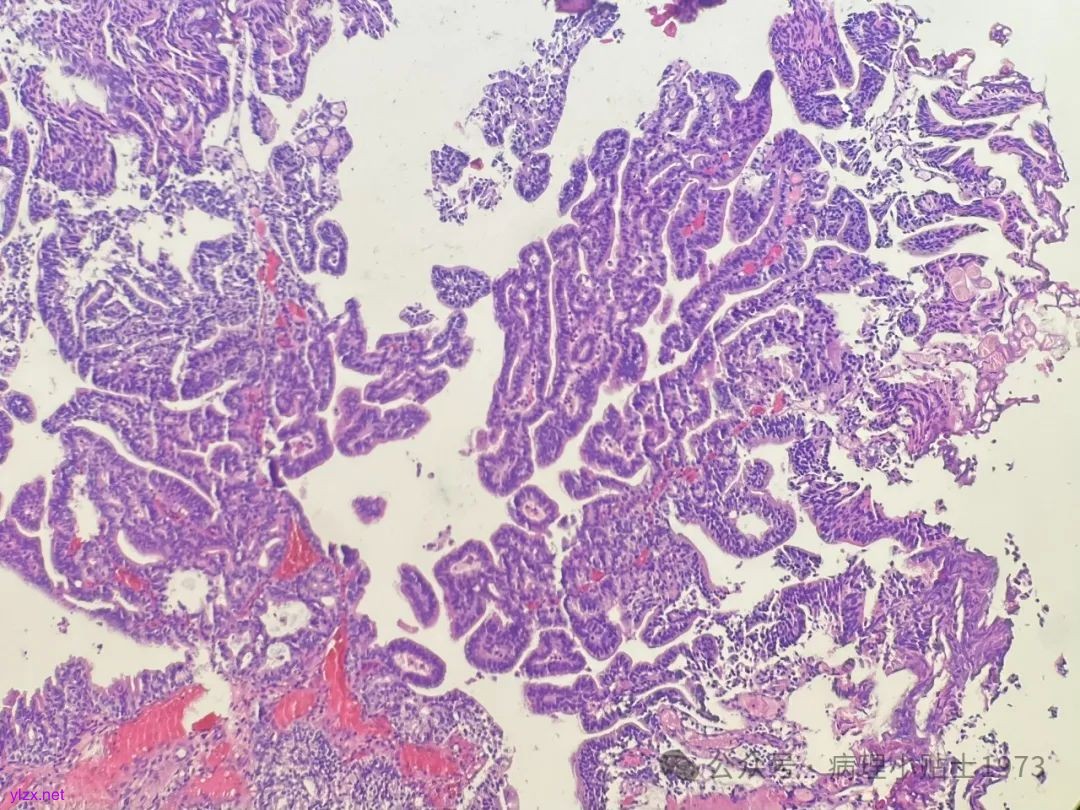

02 病例切片

诊断:非浸润性乳头状尿路上皮癌伴显著腺性分化

问题一:本病例出现了显著的腺性分化,不要误诊为单纯的腺癌。仔细寻找,仍然可以见到复层排列的经典尿路上皮癌成分。

问题二:本病例的肿瘤极性轻度紊乱,细胞核轻度到中度异型,部分可见清晰小核仁清晰,凋亡易见,免疫组化弥漫表达p16和CK20(弥漫阳性多见于高级别病变),ki67指数较高。到底该归入低级别还是高级别病变呢?